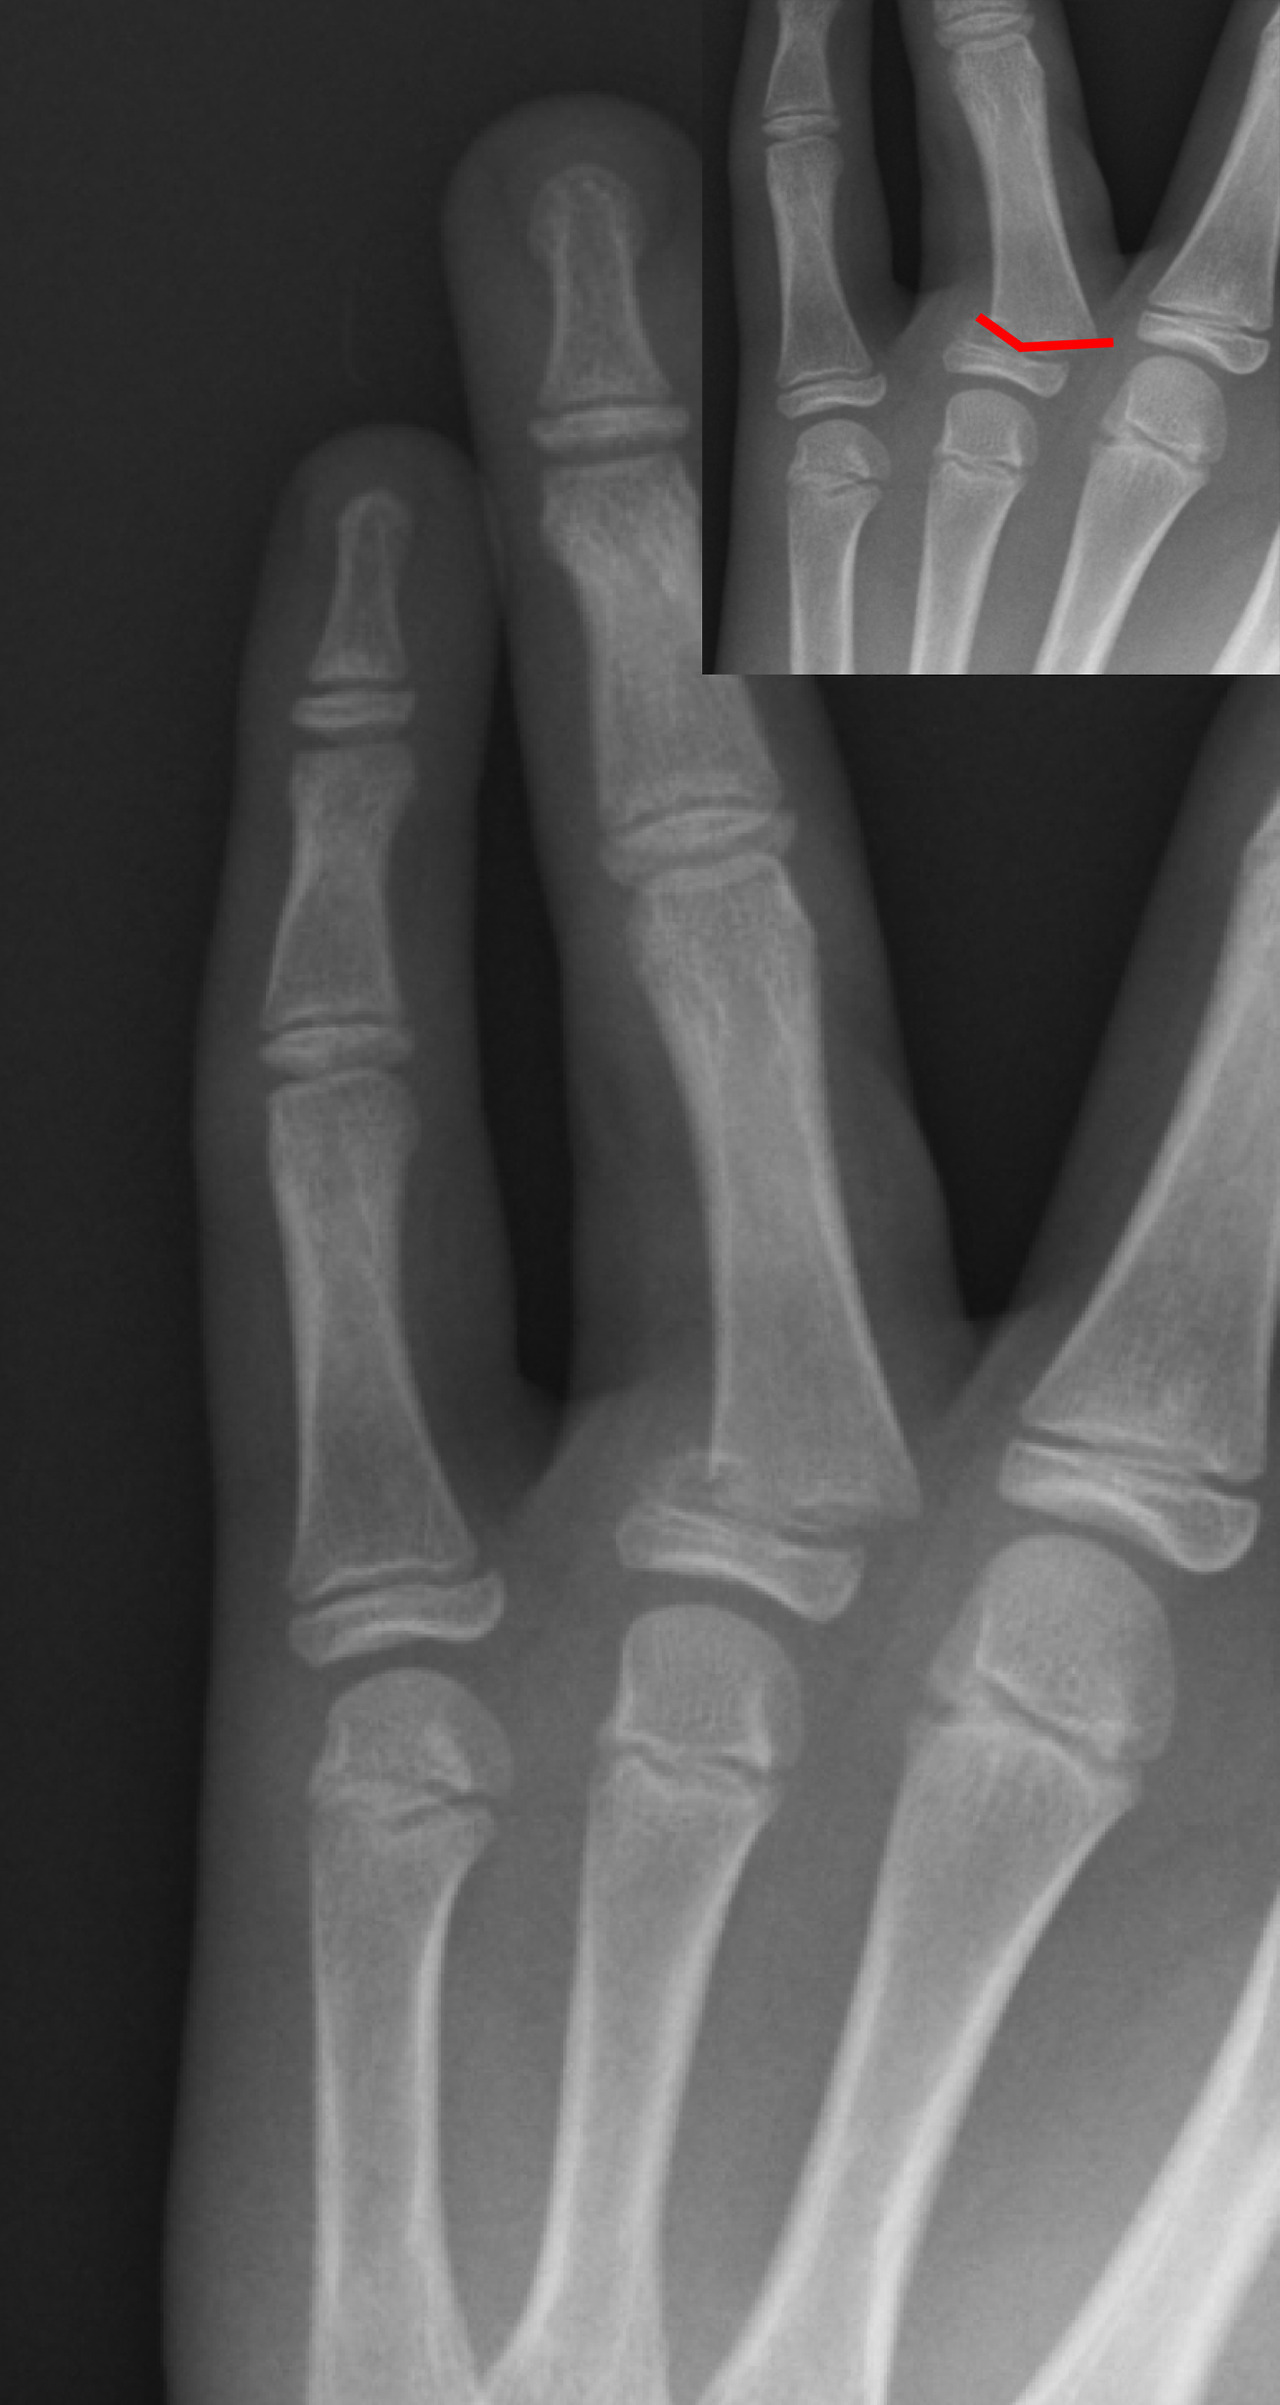

발가락 골절은 말 그대로 발가락 뼈(지골)에 금이 가거나 완전히 부러지는 상황을 뜻합니다. 일상 속 작은 충격부터, 스포츠 활동 중 강한 타격까지 다양한 원인으로 생길 수 있습니다. 특히 발가락 끝이 가구에 부딪히는 사소한 실수로도 골절이 발생할 수 있어, “정말 작게 다쳤는데 의외로 크게 아프다”라는 말을 자주 듣게 됩니다.

골절 유형

- 단순 골절: 뼈가 한 번 금이 가거나 깨진 정도로, 비교적 뼈 조각이 많이 어긋나지 않은 경우입니다.

- 복합 골절: 뼈가 여러 조각으로 나뉘거나, 뼈가 제 위치에서 크게 어긋난 경우입니다.

- 압박 골절: 압력에 의해 납작하게 뭉개지듯 부러진 형태이며, 골절 부위가 복합적으로 손상되기 쉽습니다.